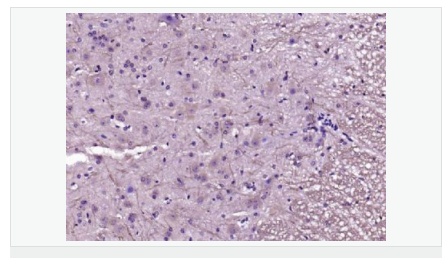

| 產(chǎn)品應用 | WB=1:500-2000 IHC-P=1:100-500 IHC-F=1:100-500 Flow-Cyt=1μg/Test ICC=1:100-500 IF=1:100-500 (石蠟切片需做抗原修復) not yet tested in other applications. optimal dilutions/concentrations should be determined by the end user. |

| 產(chǎn)品介紹 | This gene encodes a member of the membrane-associated guanylate kinase (MAGUK) family. It heteromultimerizes with another MAGUK protein, DLG2, and is recruited into NMDA receptor and potassium channel clusters. These two MAGUK proteins may interact at postsynaptic sites to form a multimeric scaffold for the clustering of receptors, ion channels, and associated signaling proteins. Multiple transcript variants encoding different isoforms have been found for this gene. [provided by RefSeq, Jul 2008] Function: Interacts with the cytoplasmic tail of NMDA receptor subunits and shaker-type potassium channels. Required for synaptic plasticity associated with NMDA receptor signaling. Overexpression or depletion of DLG4 changes the ratio of excitatory to inhibitory synapses in hippocampal neurons. May reduce the amplitude of ACCN3 acid-evoked currents by retaining the channel intracellularly. May regulate the intracellular trafficking of ADR1B. Subunit: Interacts with ANKS1B, KLHL17 and PRR7. Interacts through its PDZ domains with NETO1. Interacts through its first two PDZ domains with GRIN2A, GRIN2B, GRIN2C, GRIN2D, ACCN3, certain splice forms of GRIN1, KCND2, CXADR and SYNGAP1. Interacts through its second PDZ domain with the PDZ domain of NOS1 or the C-terminus of CAPON. May interact with HTR2A. Interacts through its guanylate kinase-like domain with DLGAP1/GKAP, DLGAP2, DLGAP3, DLGAP4, MAP1A and BEGAIN. Interacts through its third PDZ domain with CRIPT (By similarity). Interacts through its first two PDZ domains with KCNA1, KCNA2, KCNA3, KCNA4 and ERBB4. Interacts through its first PDZ domain with GRIK2, KCNA4 and CRIPT. Interacts through its third PDZ domain with NLGN1, and probably with NLGN2 and NLGN3. Interacts through its guanylate kinase-like domain with KIF13B. Isoform 2 interacts through an L27 domain with HGS/HRS and the first L27 domain of CASK. Interacts with LRFN1, LRFN2 and LRFN4. Interacts with ANO2, ADAM22 and LGI1. Interacts with FRMPD4 (via C-terminus). Interacts (via PDZ1 and PDZ2 domains) with LRRC4; LRRC4B and SEMA4C. Interacts (via guanylate kinase-like domain) with SIPA1L1. Subcellular Location: Cell membrane; Peripheral membrane protein. Cell junction, synapse, postsynaptic cell membrane, postsynaptic density. Cell junction, synapse. Cell junction, synapse, synaptosome. Note=High levels in postsynaptic density of neurons in the forebrain. Also in presynaptic region of inhibitory synapses formed by cerebellar basket cells on axon hillocks of Purkinje cells. Tissue Specificity: Brain. Post-translational modifications: Palmitoylation of isoform 1 is required for targeting to postsynaptic density. Similarity: Belongs to the MAGUK family. Contains 1 guanylate kinase-like domain. Contains 3 PDZ (DHR) domains. Contains 1 SH3 domain. SWISS: P78352 Gene ID: 1742 Database links: Entrez Gene: 1742 Human Entrez Gene: 13385 Mouse Omim: 602887 Human SwissProt: P78352 Human SwissProt: Q62108 Mouse Unigene: 463928 Human Unigene: 27256 Mouse Unigene: 9765 Rat Important Note: This product as supplied is intended for research use only, not for use in human, therapeutic or diagnostic applications. 該蛋白質(zhì)PSD95能夠幫助建立神經(jīng)突觸的架構(gòu),并且促成突觸其他部分的成熟,例如加強目標細胞上的glutamate受體的聚集、增加樹突棘(dendritic spines)的數(shù)量和大小以及增加神經(jīng)傳導物質(zhì)glutamate (谷氨酸鹽)釋放的量。這種蛋白質(zhì)與阿滋海默癥有關(guān)。 |